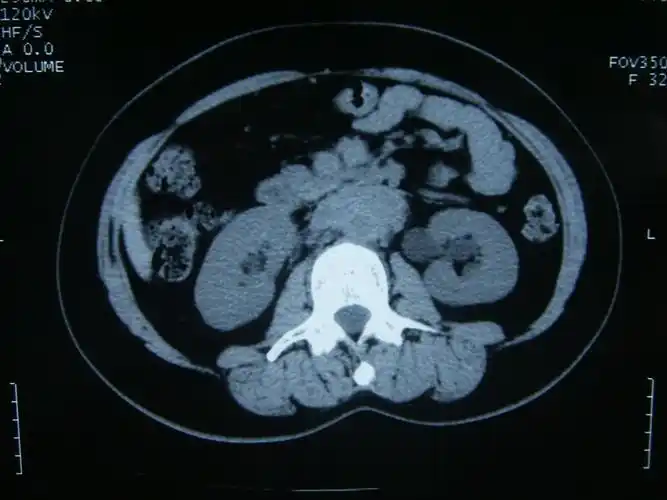

看图讨论一例肾积水病人